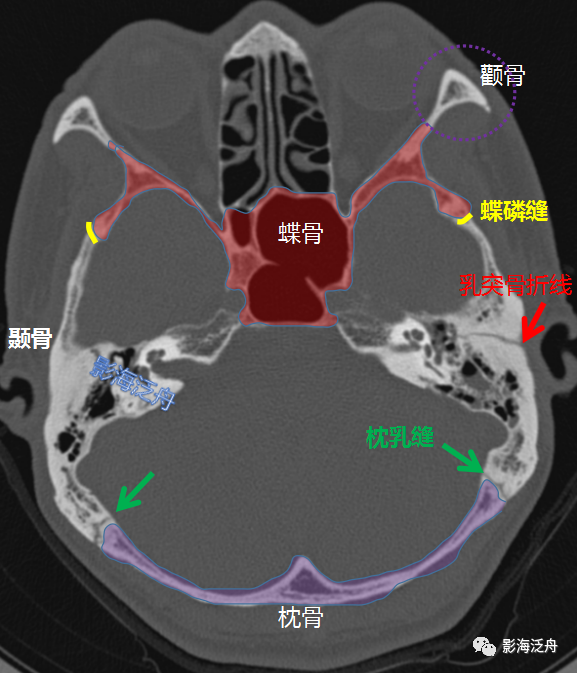

颅底ct高清图解 常见骨折部位图示_影像诊断中心